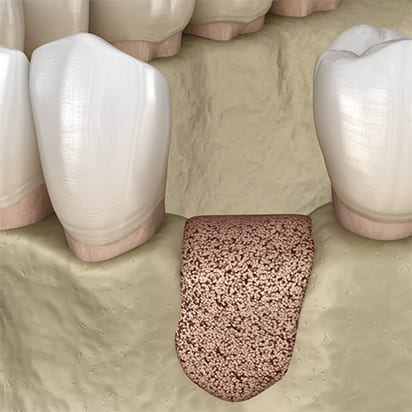

Depending on your particular case we will use either particle graft material, or block grafts, or both. Particle graft material is packed into and around an area with insufficient bone, whereas block grafts are screwed into the jawbone.

Particle graft material: